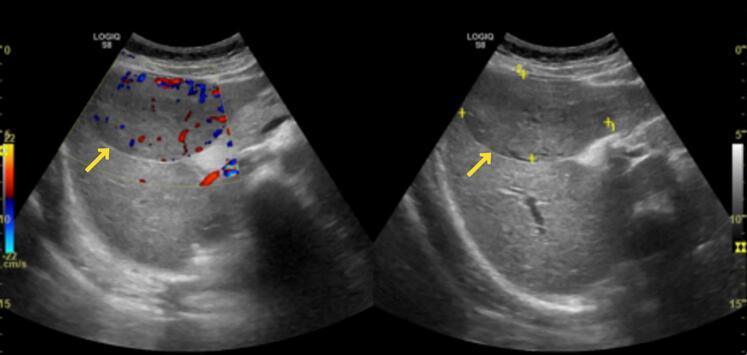

A 24-year-old pregnant female, in her fifth month of pregnancy, presented with right hypochondrium pain and nausea. Radiological imaging suggested the possibility of a hepatic adenoma. The patient opted to continue the pregnancy with regular monitoring of the mass as well as fetal health. After delivering a healthy baby, the patient underwent successful mass excision and cholecystectomy. Histopathology of the liver mass confirmed the diagnosis of epithelioid HAML.

一名24岁的妊娠女性,孕5个月,出现右季肋部疼痛和恶心。影像学检查提示肝腺瘤的可能性。患者选择继续妊娠,同时定期监测肿块及胎儿健康状况。在分娩出一名健康婴儿后,患者成功接受了肿块切除和胆囊切除术。肝脏肿块的组织病理学检查确诊为上皮样HAML。